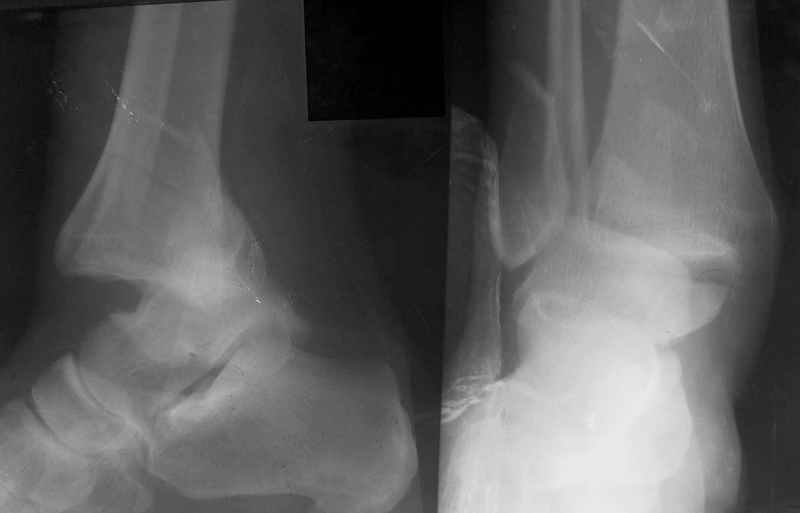

Ответы на вопросы: 1. Дистракцию снять! Все правильно вы понимаете: наружная лодыжка -ключ г\ст сустава, а пытаетесь наоборот - таранную кость сделать "ключом"... Нейротрофические расстройства очень могут появиться..

2. Конечно аппарат собран не лучшим образом. База на стопе очень низко расположена, есть даже сомнения: обе ли спицы проходят через пяточную кость? Откройте любое руководство по чрескостному остеосинтезу и найдете ответ на вопрос, как компоновать аппарат, возможно, даже удивитесь, когда узнаете , что есть компановки вообще не фиксирующие г\ст сустав.

3. Если добиваться в аппарате, то только путем проведения дополнительных спиц и небольшого перемонтажа... Диастаз говорит только о неанатомичной репозиции лодыжки, со всеми вытеающими...

Слышали ли Вы о принципах хирургического лечения внутрисуставных переломов, таких как 1.анатомичная репозиция,

2.внутренняя (хотя и наружняя тоже может быть)фиксация отломков (а не сустава)по принципу "абсолютной" стабильности,

3.атравматичная техника

4 ранняя мобилизация сустава (а возможно и ранняя нагрузка, если вдавления хряща нет)???

Вообщем, еще не поздно (и совершенно неопасно) снять аппарат, и сделать открытую репозицию и полноценный остеосинтез наружной лодыжки стягиваающим винтом и нейтрализующей 1\3-трубчатой пластиной... Лучше это было сделать сразу при поступлении в качестве экстренной операции, крнечно если есть возможность, а она всегда будет, если есть желание!!

Стабильность г\ст сустава обеспечивается во-первых наружной лодыжкой (ключ), во-вторых задним краем б\б кости, в-третьих связками синдесмоза и межкостной мемраной, только в-четвертых медиальной лодыжкой (дельтовидной связкой. Это классика! А пяточной кости и плюсневых костей здесь нет! зачем их фиксировать? см. вложенный файл.